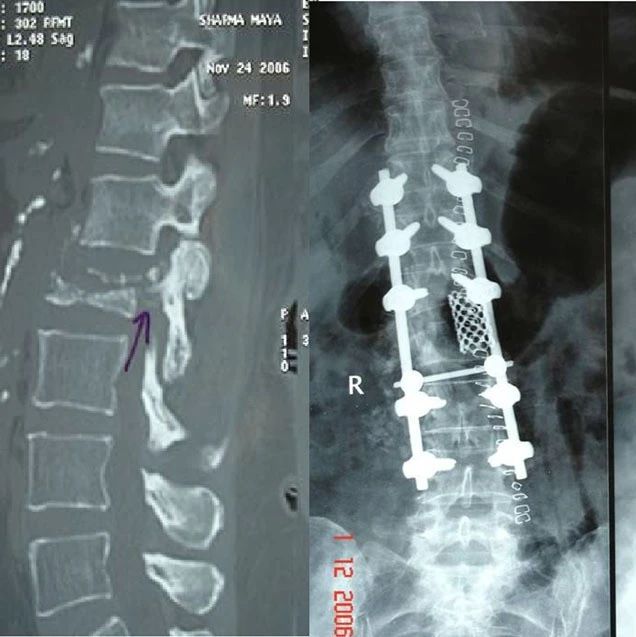

骨质疏松性椎体压缩性骨折的手术策略:Patil分型

骨质疏松性压缩骨折(OVCF)的发生率逐年上升,其中约1/3患者表现为伴有或不伴有神经功能损伤的症状性骨不连。尽管其中大部分可以通过椎体成形术进行治疗,但仍有一部分伴有神经功能损伤患者不适合进行这种治疗。2012年,Patil教授及其团队描述了OVCFs的各种类型及手术策略的选择,研究结果发表于《European Spine Journal》杂志。研究回顾分析了40例有症状的OVCF患者,其中包括了无神经功能缺损,但接受3个月保守治疗后骨折未愈合的患者,以及有神经功能损伤并立即接受手术的患者。根据患者的症状以及骨折类型,共制定了4种手术策略:...